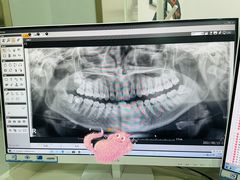

• -牙博士口腔品牌连锁(杨浦店)

夏日莫莫茶 | 21-08-13